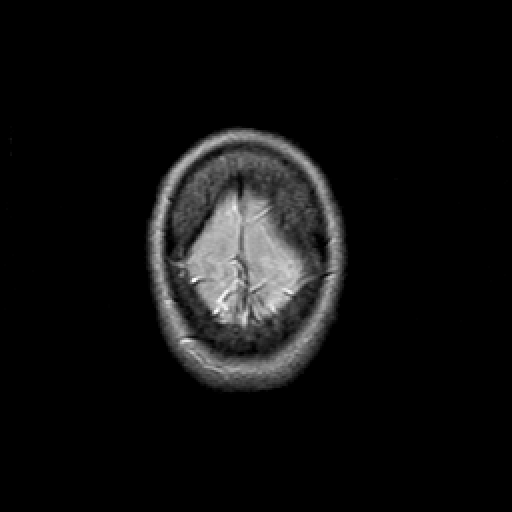

Proton density-weighted structural MR: Slice 49

Slice 49